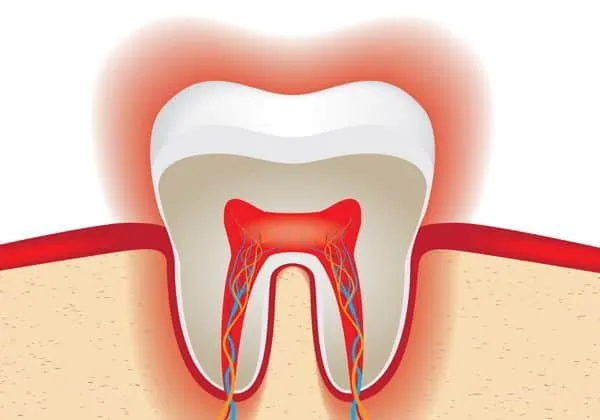

Tooth sensitivity is a complex phenomenon tied closely to the anatomy of the tooth. The outer layer, the enamel, is the hardest substance in the human body and protects the inner layers. Beneath the enamel lies the dentin, which contains thousands of tiny tubules. These tubules house fluid-filled channels that lead to the tooth’s pulp, where the nerves and blood vessels reside. When the enamel is thinned or compromised, or when the tubules are exposed, external stimuli such as hot, cold, acidic, or sweet substances can stimulate the nerves in the pulp, leading to the sensation of sensitivity. Whitening agents work by penetrating the enamel, and this can temporarily make the tubules more susceptible to these stimuli, leading to heightened sensitivity. This is a normal reaction for some individuals.